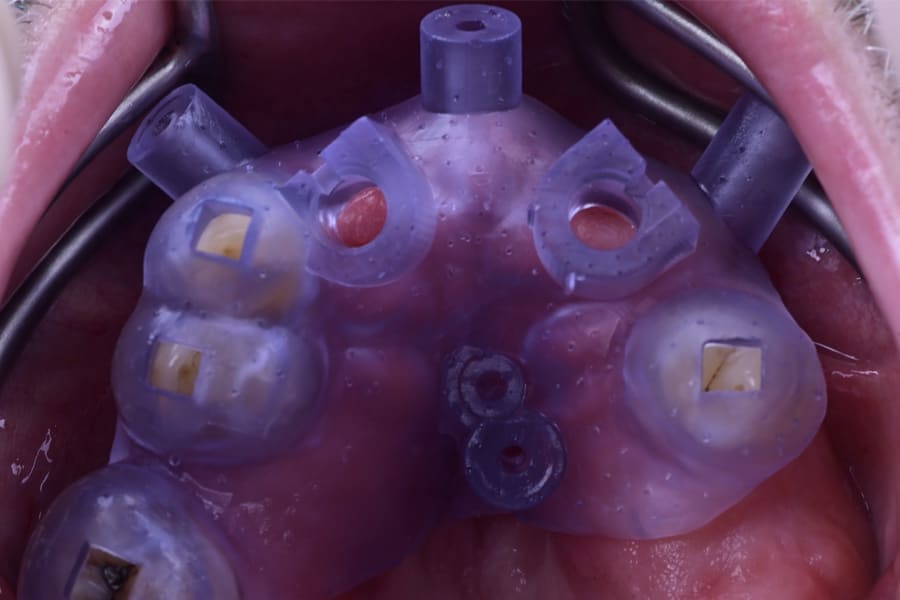

Surgical procedures performed in the maxillary jaw with the different 3D-printed surgical guides are depicted in Figure 8 through Figure 15. These surgical procedures were also done in the mandibular jaw.

Surgical guides were designed based on the prosthetic setup and fabricated by 3D printing. Guide stability was reinforced by anchor pins, ensuring accurate transfer of the plan to the surgical field. This approach provided high predictability for flapless implant placement.